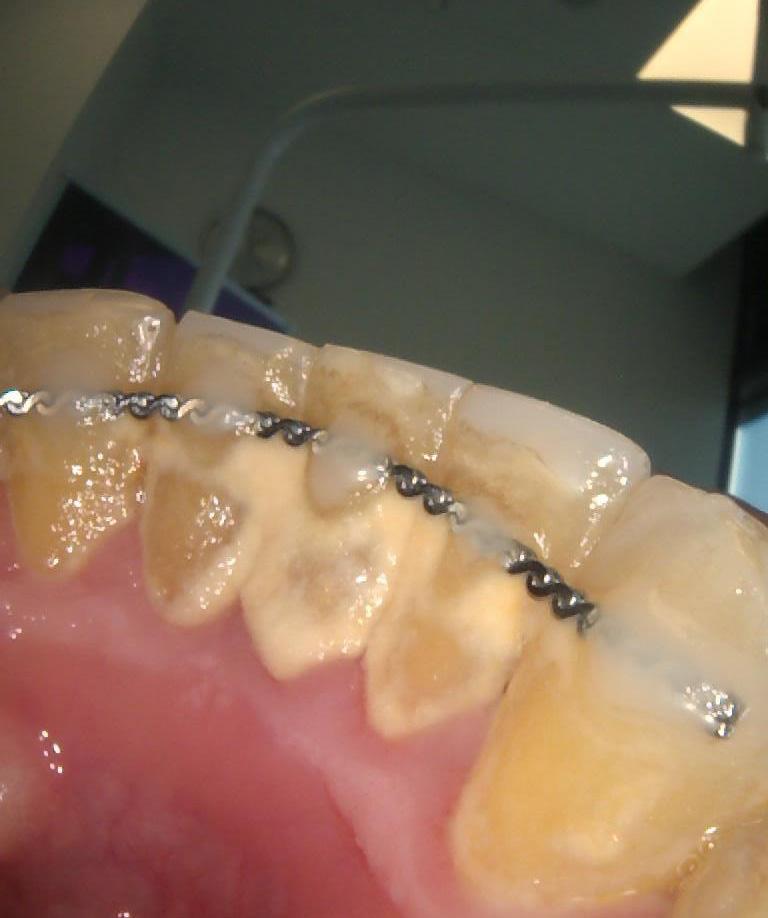

Pod opieką Agnieszki Łukowicz, Master of Science Orthodontics została poddana zaawansowanemu leczeniu aparatem stałym ligaturowym, Dzięki czemu udało się osiągnąć znaczące zmiany:

poszerzenie luków zębowych,

korekta tyłozgryzu,

rozwiązanie stłoczenia,

odrotowanie zrotowanych zębów,

odbudowa startych zębów.

Efekt estetyczny został dopełniony przez wybielanie zębów i odbudowę kompozytową wykonaną przez dr Monikę Niewitecką.

Przedstawiamy piękny i zdrowy uśmiech naszej Pacjentki!